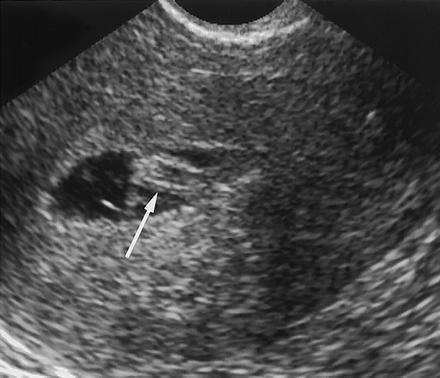

High or low-quality embryos were placed in a channel created between two strips of the womb cells.

Cells from women with normal fertility started to grow and reach out towards the high-quality embryos. Poor-quality embryos were ignored.

However, the cells of women who had recurrent miscarriages started to grow towards both kinds of embryo.